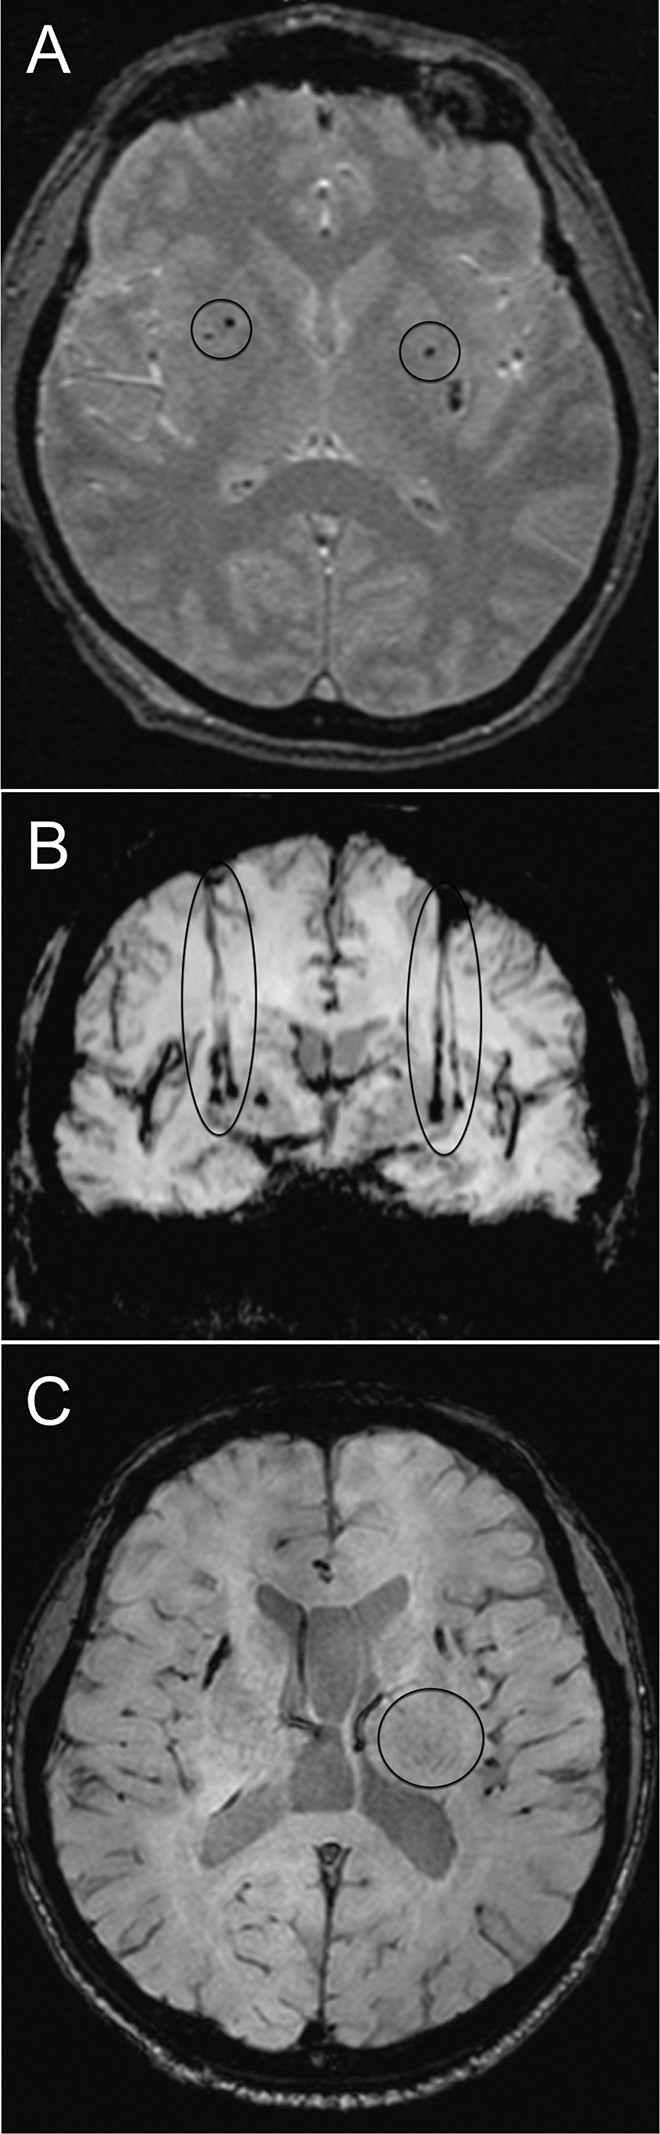

磁共振成像

移植患者的代表性腦部 MR 圖像

如圖2所示。細胞植入的位點和軌跡路徑如圖 1 和 2 所示。分別參見圖 2A 和 2B。在1、2和4年隨訪的幾個針跡結束時,在 T2 加權圖像上識別出小簇低信號。在 P4 的年度 MRI 監(jiān)測中,在右側殼核(圖2C)中觀察到強大的移植物生長,沒有大腦結構的異常。未顯示腫瘤形成的證據。